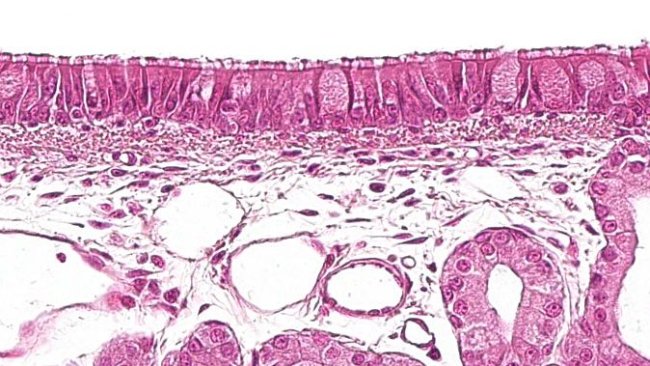

En la figura 1, podemos apreciar como M. hyopneumoniae es el agente que participa en la mayoría de las coinfecciones encontradas en el pulmón de animales diagnosticados en casos de CRP. Este patógeno, que ataca los cilios de las células del epitelio de bronquios y bronquiolos, alterando el aparato mucociliar, también provoca una hiperplasia del tejido linfoide asociado a la mucosa respiratoria. Ambas acciones favorecen la colonización, proliferación y mecanismos patogénicos de otros agentes, tanto primarios como secundarios, que afectan al aparato respiratorio del cerdo. En diferentes estudios experimentales se ha podido comprobar que, además de favorecer la acción de otros patógenos, suele potenciarla, por lo que las combinaciones en las que aparece M. hyopneumoniae suelen ser las que peores consecuencias tienen para los animales afectados, y por tanto, para la rentabilidad de la granja.